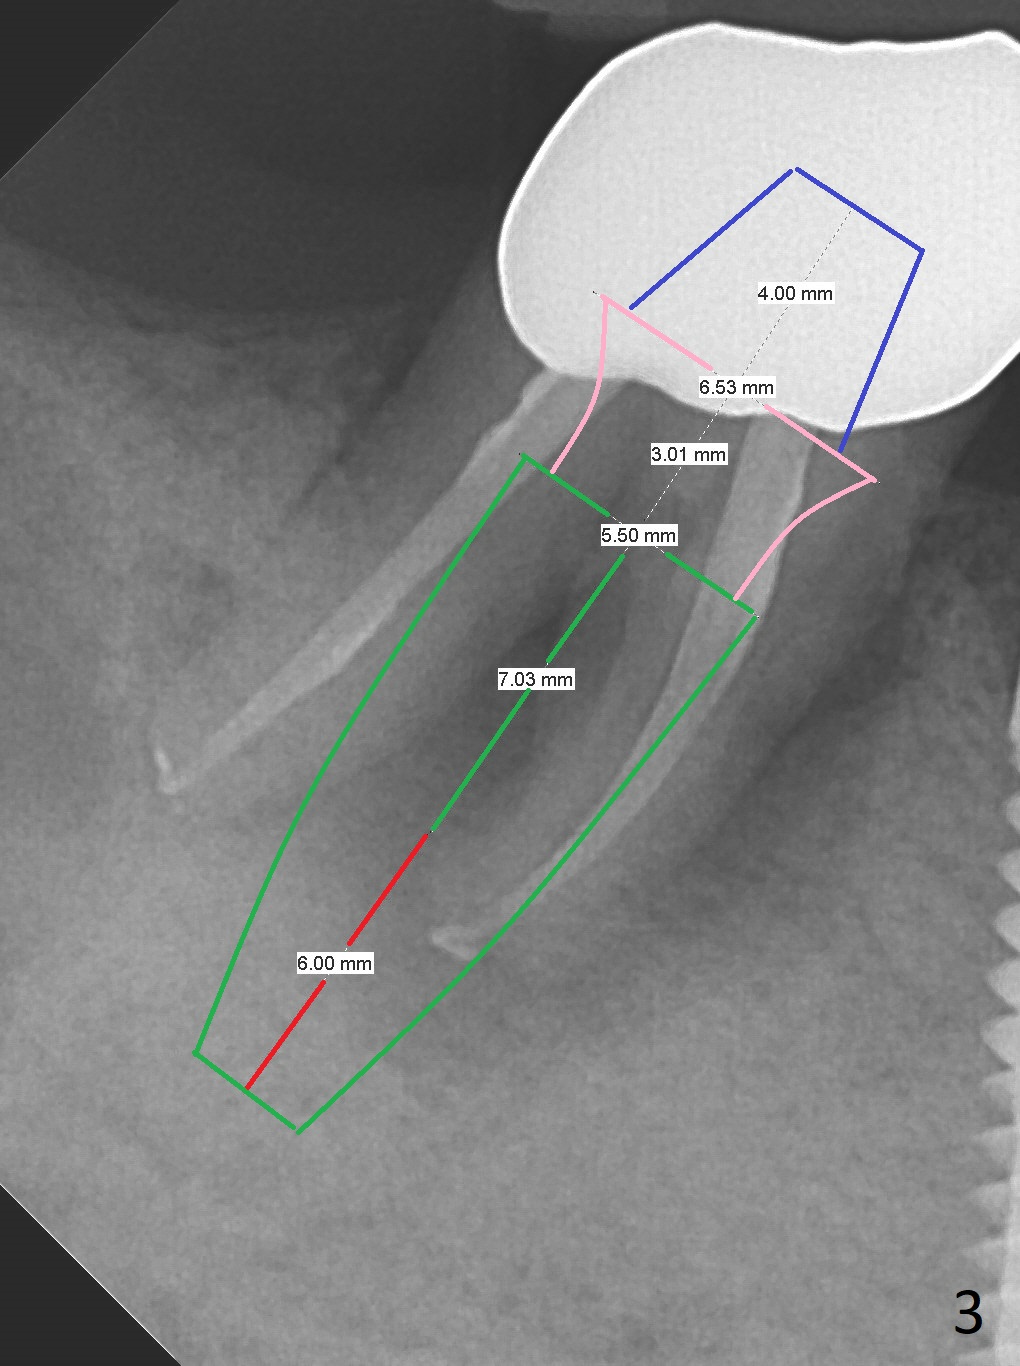

A 87-year-old man was asymptomatic with the tooth #31 eight months earlier (Fig.1), as compared to now (Fig.2). After extraction, osteotomy will be initiated in the septum (where there is more bone height) using IS 6 mm stopper (Fig.3 red line), followed by PA. If PA does not show the Inferior Alveolar Canal (Fig.1 red dashed line), take panoramic X-ray. A 5.5x13 mm implant will be placed (7 mm may not be covered by the native bone). The mesial root vertical root fracture is more obvious 7 months later (Fig.4,5).